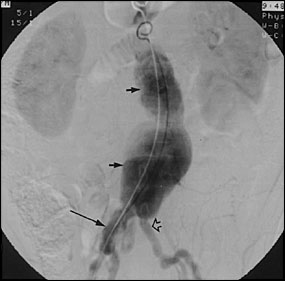

An aortic aneurysm involves the aorta, the major artery that leaves the heart to supply blood to the body. An aortic aneurysm is a dilation or bulging of the aorta..

Most aortic aneurysms are fusiform. They are shaped like a spindle (“fusus” means spindle in Latin) with widening all around the circumference of the aorta. (Saccular aneurysms just involve a portion of the aortic wall with a localized out pocketing).

Aortic aneurysms can develop anywhere along the length of the aorta but the majority are located in the abdominal aorta. Most of these abdominal aneurysms are located below the level of the renal arteries, the vessels that provide blood to the kidneys. Abdominal aortic aneurysms can extend into the iliac arteries.